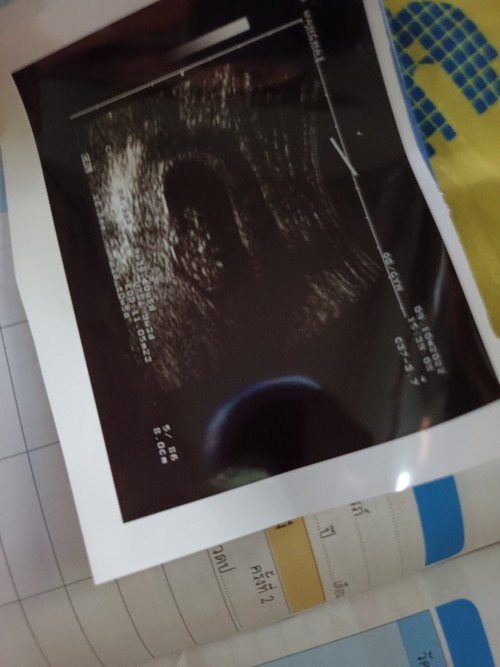

แม่ๆบ้านไหนกำหนดคลอดเดือน5บ้าง แม่บ้านนี้20พฤษภาคม 66